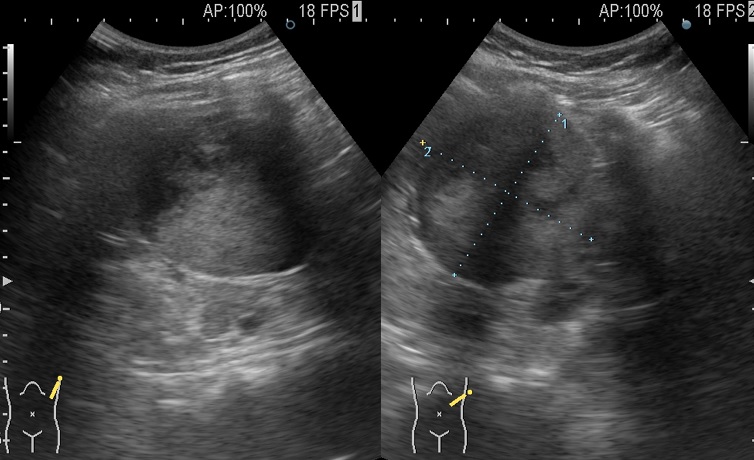

脾腫瘍

2日前よりクシャミやあくびをすると左季肋部に痛みが出て来院された27歳男性。

99%肋間神経痛だろうと思い、念のため行ったエコー検査で脾臓に73mmの球形腫瘍を認めたため外科病院を紹介した

手術の結果は脾過誤腫(良性)であった。珍しいケースである。